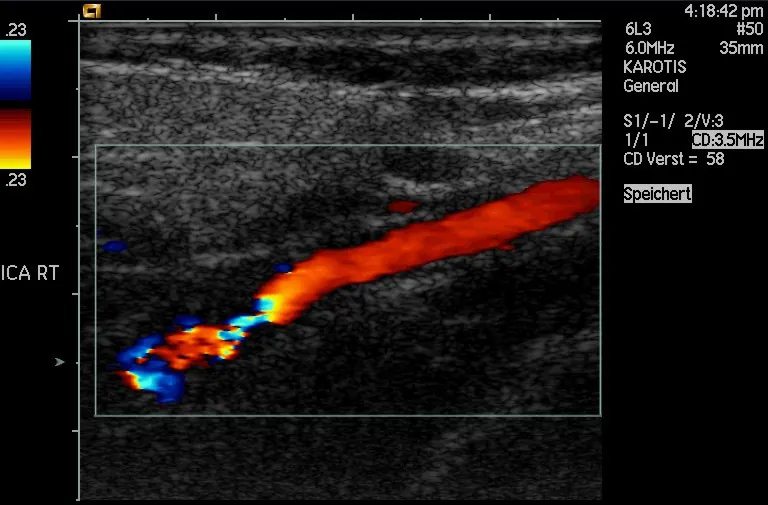

Another major use of ultrasound in medical diagnostics is to detect motion and determine velocity through the Doppler shift of an echo, known as Doppler-shifted ultrasound. This technique is used to monitor fetal heartbeat, measure blood velocity, and detect occlusions in blood vessels, for example. (See Figure 17.49.) The magnitude of the Doppler shift in an echo is directly proportional to the velocity of whatever reflects the sound. Because an echo is involved, there is actually a double shift. The first occurs because the reflector (say a fetal heart) is a moving observer and receives a Doppler-shifted frequency. The reflector then acts as a moving source, producing a second Doppler shift.

Doppler-shifted ultrasonic image of a partially occluded artery.

Figure 17.49 This Doppler-shifted ultrasonic image of a partially occluded artery uses color to indicate velocity. The highest velocities are in red, while the lowest are blue. The blood must move faster through the constriction to carry the same flow. (credit: Arning C, Grzyska U, Wikimedia Commons)